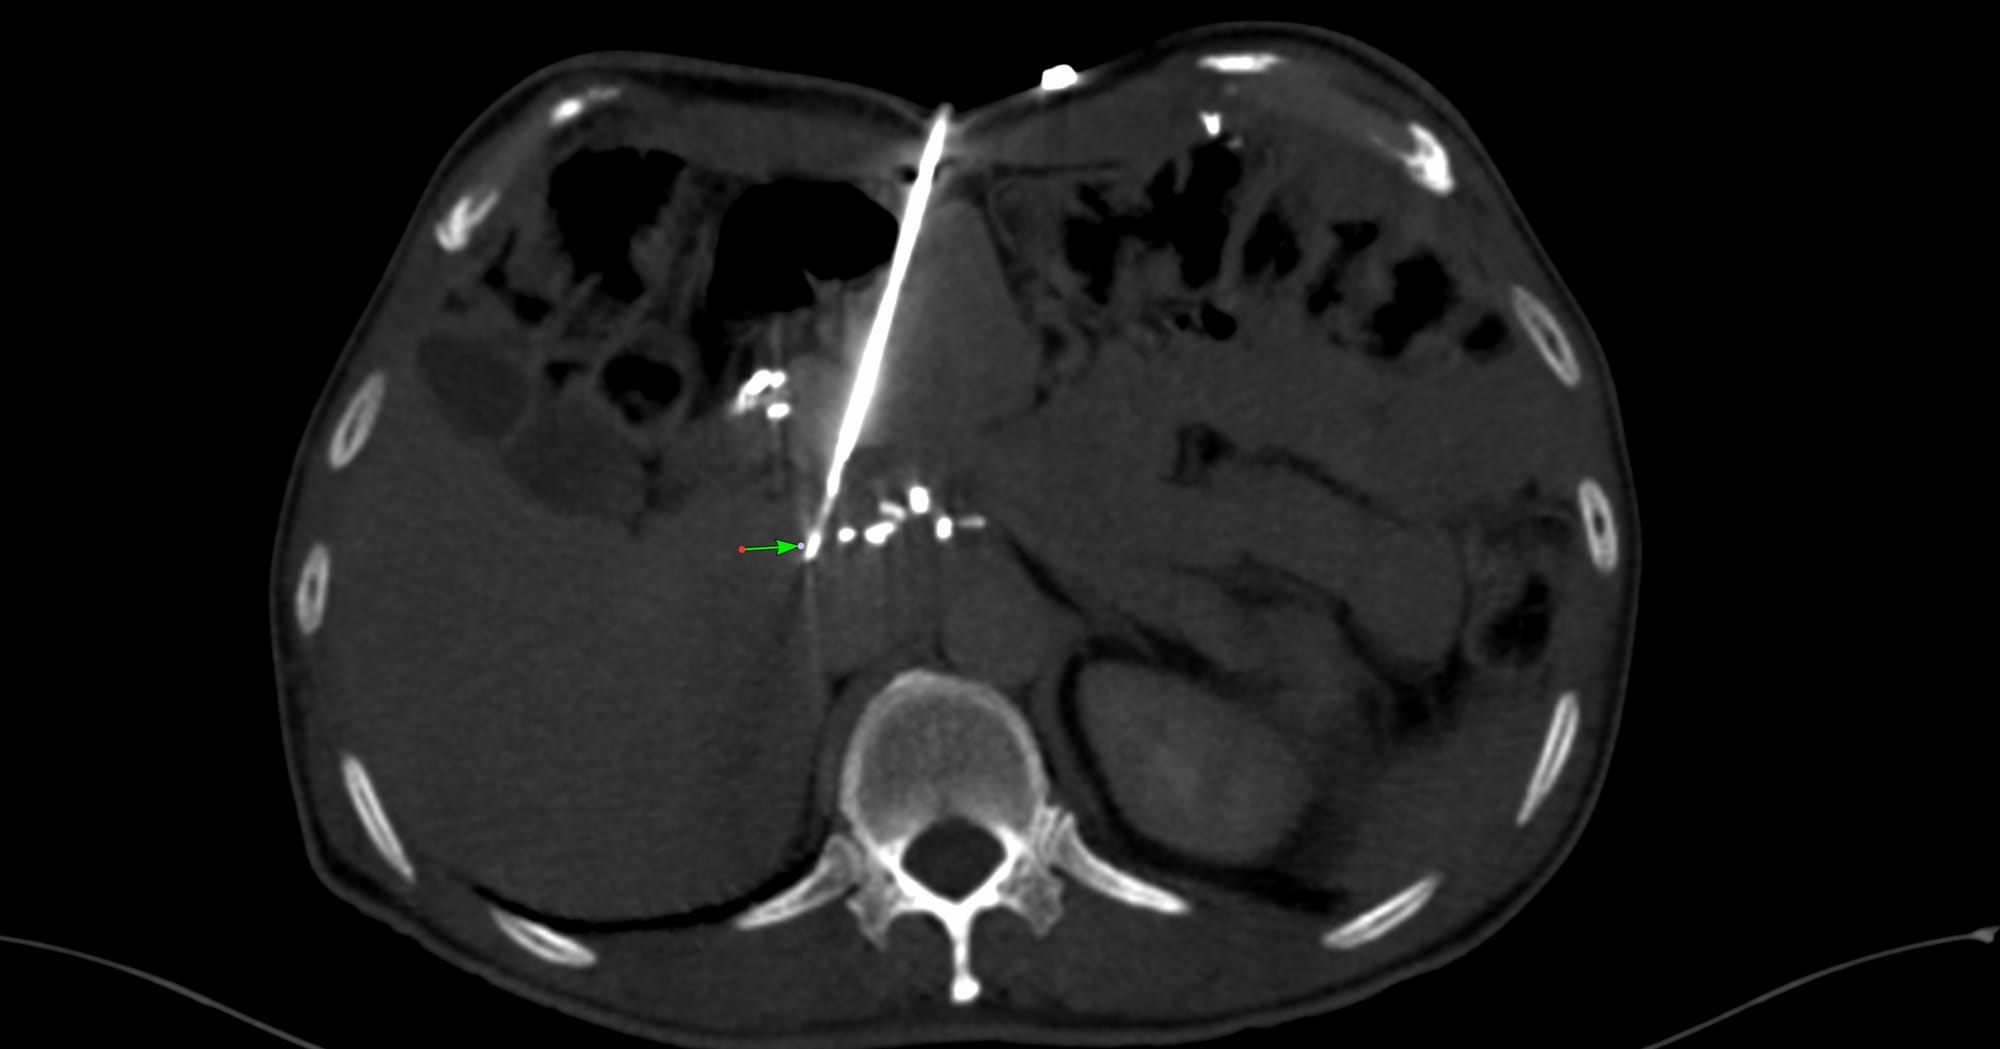

Case 173 - Periportal Node Biopsy in a Post-Whipple’s Abdomen - The Power of a Blunt-Tip Needle